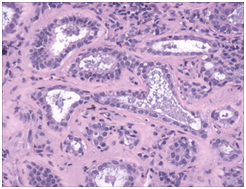

- Cervical lymph nodes with inclusions of salivary glands may exhibit expansive, reactive lymphoid follicles with prominent germinal centres with numerous tingible body macrophages, foci of monocytoid cells, immunoblasts, plasma cells and vascular proliferation. Disseminated inclusions of salivary gland ducts and acini may not manifest lymphocytic permeation and destruction, as is exemplified in Sjogren’s syndrome and Mikulicz’s disease (Figure 2 - Figure 4).3

- Salivary glands inclusions: Inclusions from the salivary glands are frequent in the upper cervical lymph nodes and may manifest as a component of the developmental embryogenesis. Intact, undamaged glandular ducts and acini may be elucidated. The lymph node may manifest reactive follicles with prominent germinal centres with numerous tingible body macrophages, plasma cells and monocytoid cells. The concordant sjogren’s & mikulicz syndrome may depict a lymphocytic infiltration of the ducts and acini.4 A malignant transformation may emerge with these inclusions, usually as a potential warthin’s tumour, a pleomorphic or a monomorphic adenoma, a mucoepidermoid carcinoma or an acinic cell carcinoma.5

Figure 2 Nevus cell inclusions containing melanin.

Figure 3 Benign mammary inclusions with glandular configuration.

Figure 4 Cystic mullerian duct inclusions in the lymph node